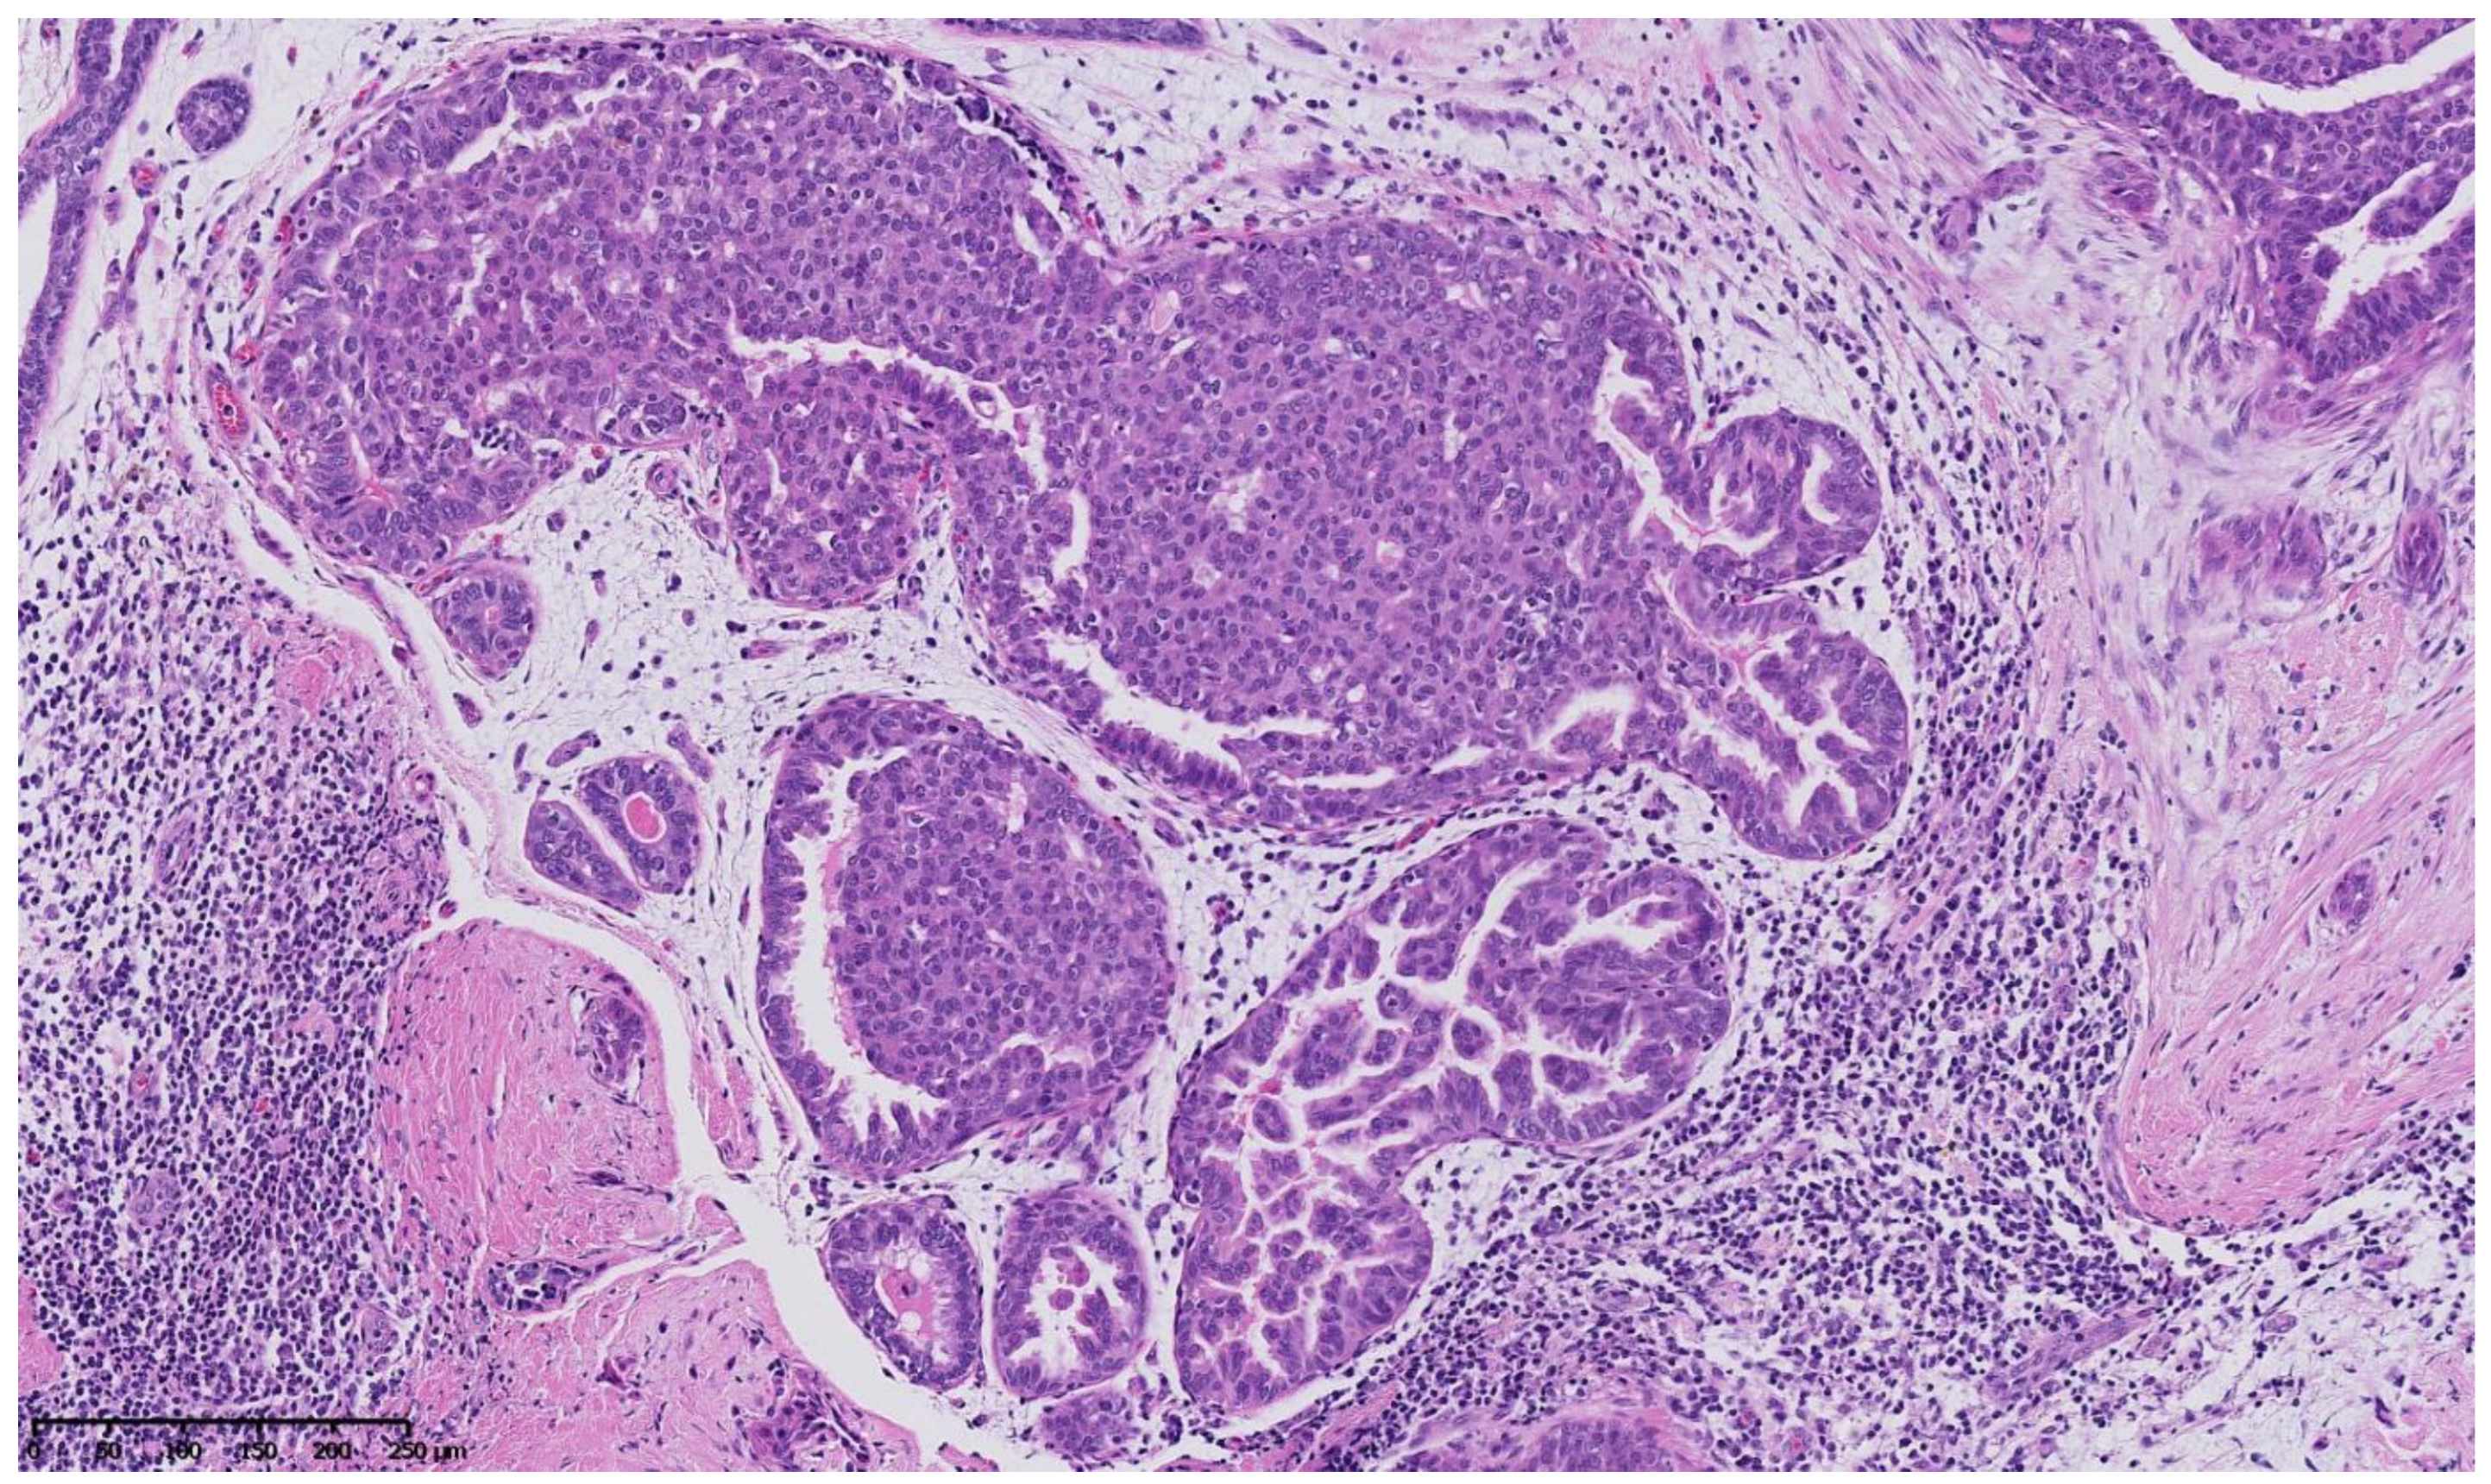

4. Benign Breast Lesions in Transwomen

5. Risk of Breast Cancer: What Do We Know?